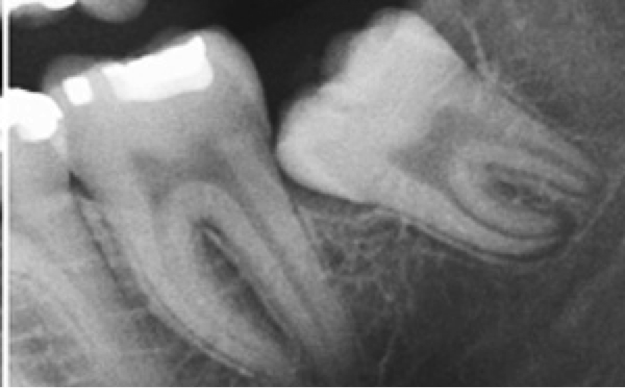

![]() |

| Α ημιέγκλειστος φρονιμίτης με κλίση εγγύς και τερηδόνα

Β δεύτερος γομφίος με τερηδόνα C φλεγμαίνουσα ουλική καλύπτρα D υπερέκφυση του πάνω φρονιμίτη |

Τώρα πώς αντιμετωπίζουμε την περιστεφανίτιδα. Κατ’ αρχάς με μία ακτινογραφία τοπική ή πανοραμική εκτιμούμε την κατάσταση, τη θέση και τη φορά ανατολής του φρονιμίτη.

| Ακτινογραφία που δείχνει τη φορά του φρονιμίτη |